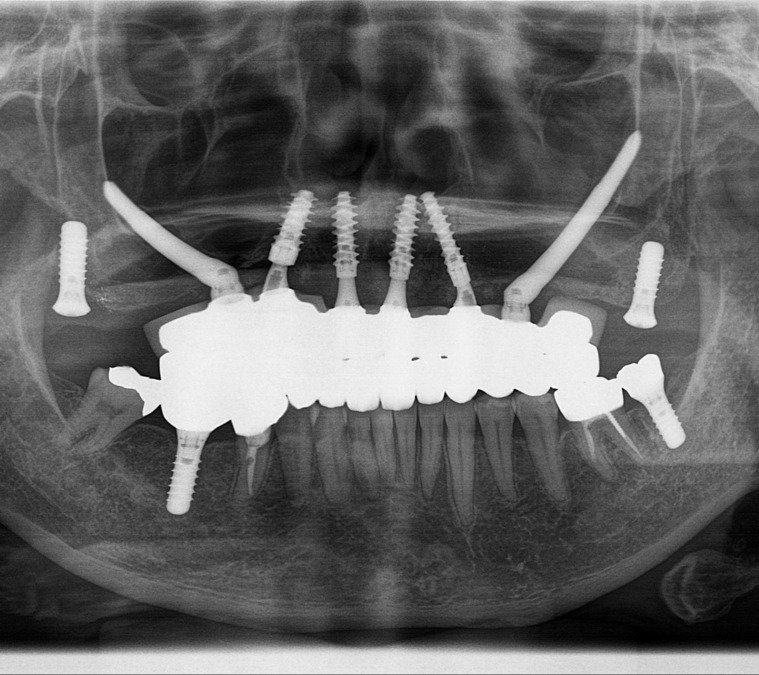

当院は自費診療を中心に行う歯科医院になります。また、インプラント治療においては症例数や専門性も高く、オールオン4やザイゴマインプラントも行っています。大阪市内ではザイゴマインプラントを施術しているところは当院のみになり、近々地方全域でもおそらく4医院のみだと思います。(大阪では当院入れて2医院)